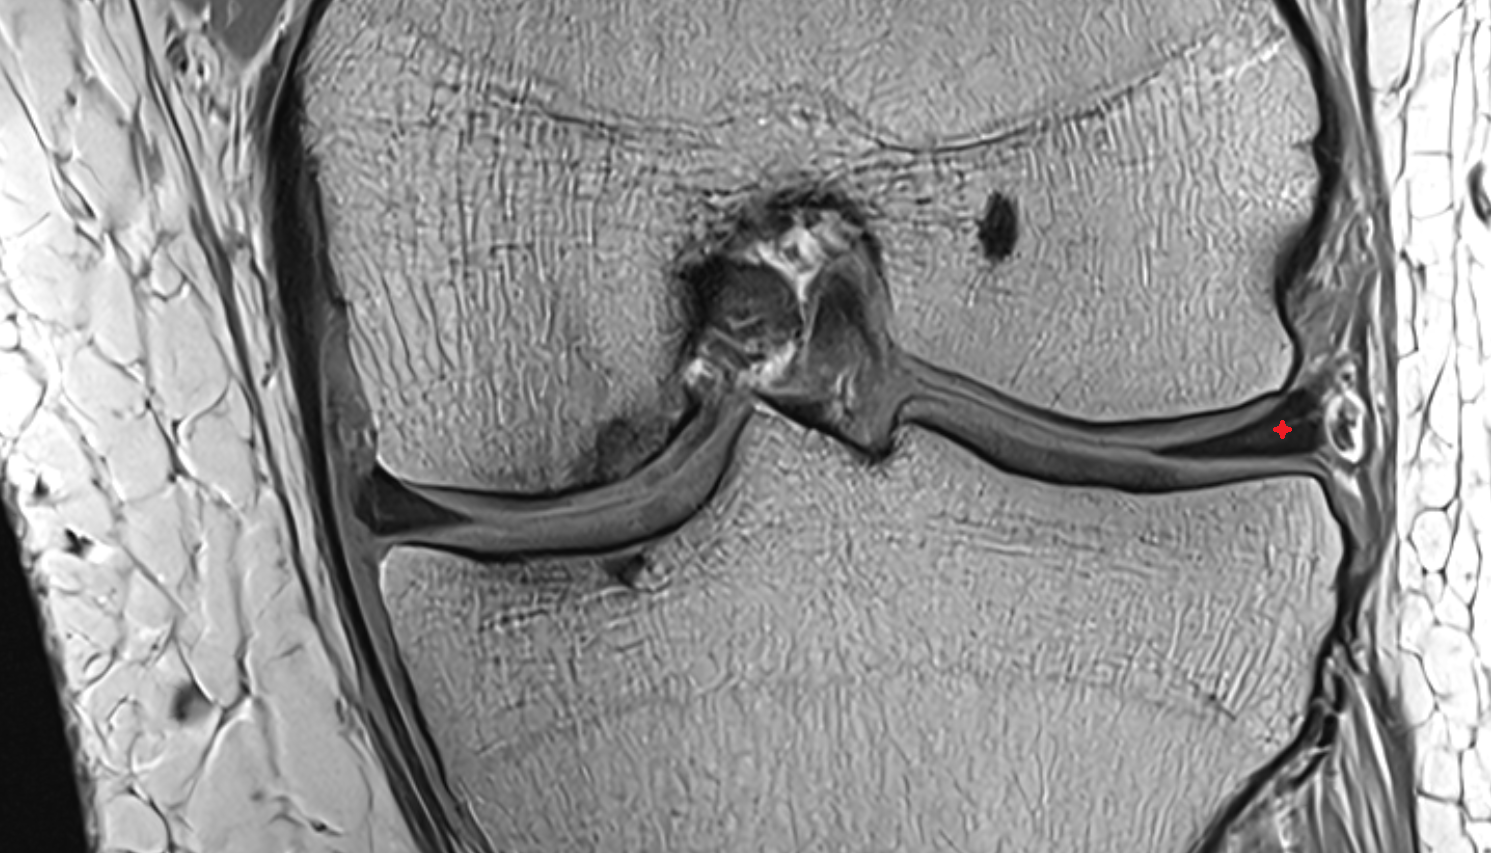

- Anterior cruciate ligament

- Posterior cruciate ligament

- Medial condyle of femur

- Femoral condyle articular cartilage

- Medial meniscus

- Lateral meniscus

- Knee Joint